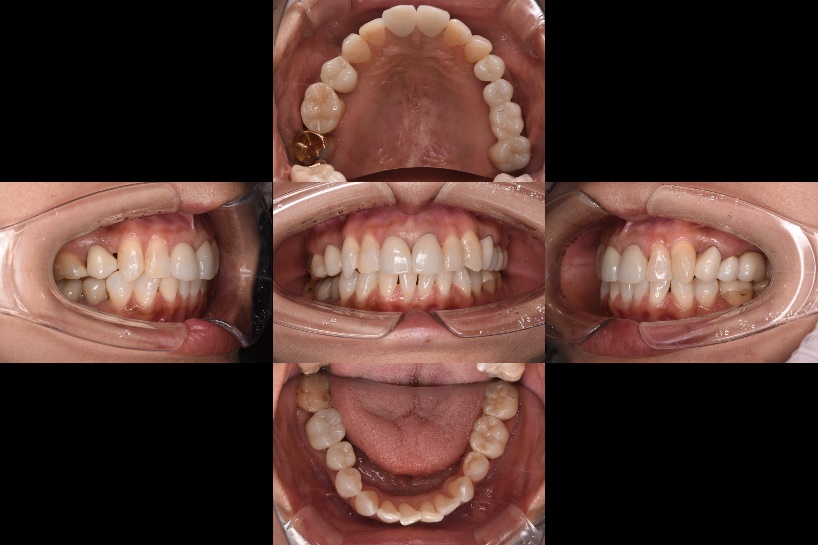

| 治療内容 | 全顎治療 |

| 主訴 | 検診希望。ちゃんとした治療を受けたい |

| 診断 | 多数の補綴物不適合 |

| 治療期間 | 5か月 |

| 治療費用 | 補綴費用¥930,000- |

| 院長コメント | 当院で全顎治療を受けられているご友人からの紹介の70代女性でした。水平にチェアを倒すとめまいがするとのことで起こし気味で治療させていただきました。数十年前に治療された金の詰め物が多数装着されていましたが、詰め物と歯との合いが悪くなってきていましたので、ご説明し、長持ちするジルコニアによる修復を計画しました。一本ずつやり替える際、かみ合わせを変えないよう、調和した補綴物となるよう心掛け、口腔内でチェックを徹底しました。また、前歯はダイレクトボンディングにて修復しました。ラバーダムを設置することで接着面を唾液から完全隔離し、最大限接着力を高めることができました。 大変きれいになったと喜んでもらえました。 |